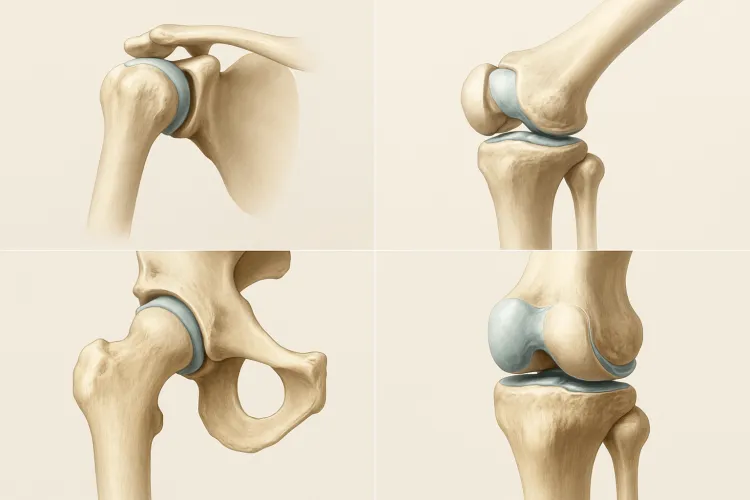

Одними из важнейших элементов опорно-двигательного аппарата являются суставы. Они представляют собой подвижные костные соединения, благодаря которым человеческий скелет способен к подвижности. С их помощью наше тело может выполнять различные движения: сгибание, разгибание, повороты, вращения, приведение, отведение. Движение тела человека начинается, прежде всего, с движения суставов. Именно поэтому так важно поддерживать их в хорошем состоянии.

Концы костей, в местах их соединения, имеют специфическую форму. Одна кость по форме выпуклая, другая с углублением. Выпуклую часть кости называют головкой сустава, а которая с углублением — ямкой. Их поверхности покрыты специальной хрящевой тканью, которая уменьшает трение, выступая неким амортизатором при резких движениях.